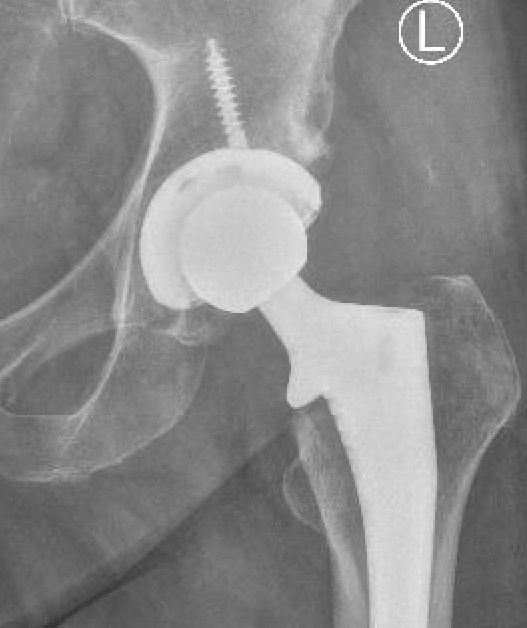

1. Acetabular Inclination

AP Xray

Excessive acetabular inclination

2. Acetabular Version

Xray

Difficult to measure on xray